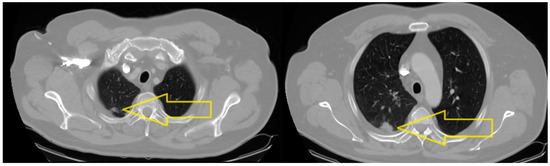

2. Case Presentation